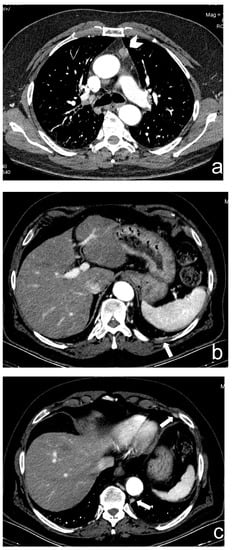

Figure 4.

(a–c) A 23-year-old man with a partially cystic lesion of the anterior mediastinum. CT scans without contrast (a) and after contrast medium administration in arterial (b) and delayed (3 min, (c)) phases show late enhancement peak of the solid component (ROI 1). Surgery revealed a seminoma.